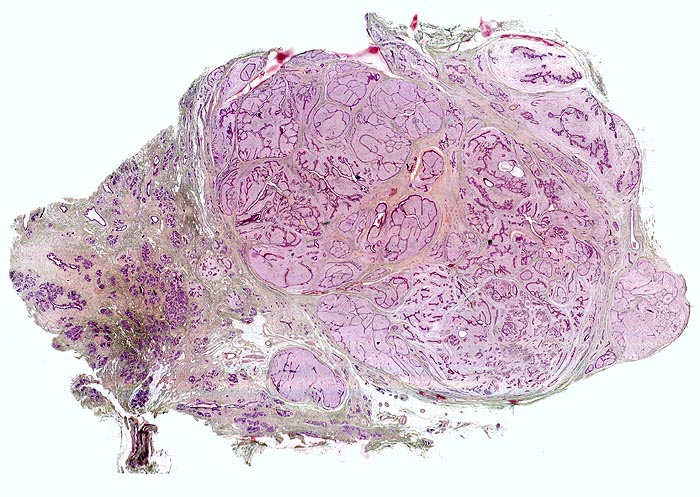

Makroskopisch haben die runden knolligen weissen Tumoren eine mittlere Grösse von 1-2cm. In 15% der Fälle finden sich multiple Fibroadenome. Auf Schnitt sind die komprimierten Gänge als spaltförmige Zeichnung erkennbar.

Das Stroma ist myxoid, fibrös-zellulär oder sklerotisch. Das zweireihige Epithel, welches die Spalten auskleidet, kann dieselben Veränderungen zeigen wie das normale Drüsenepithel (Epithelhyperplasie, Epithelmetaplasie, sklerosierende Adenose, Zystenbildung). In 0.2% aller Fibroadenome entwickelt sich ein in situ Karzinom (95%) oder ein invasives Karzinom (5%). Das juvenile Fibroadenom ist charakterisiert durch zellreiches Stroma, Epithelhyperplasie, rasches Wachstum und beträchtliche Grösse.